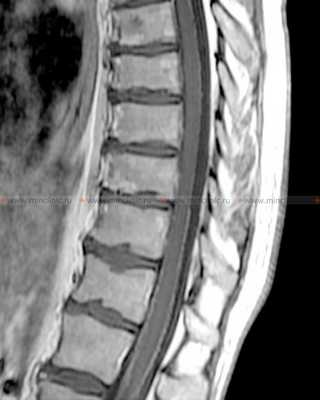

На МРТ спинного мозга после контрастирования визуализируется так называемая "сахарная глазурь" у пациентов с лептоменингеальными метастазами при канцероматозе оболочек мозга.